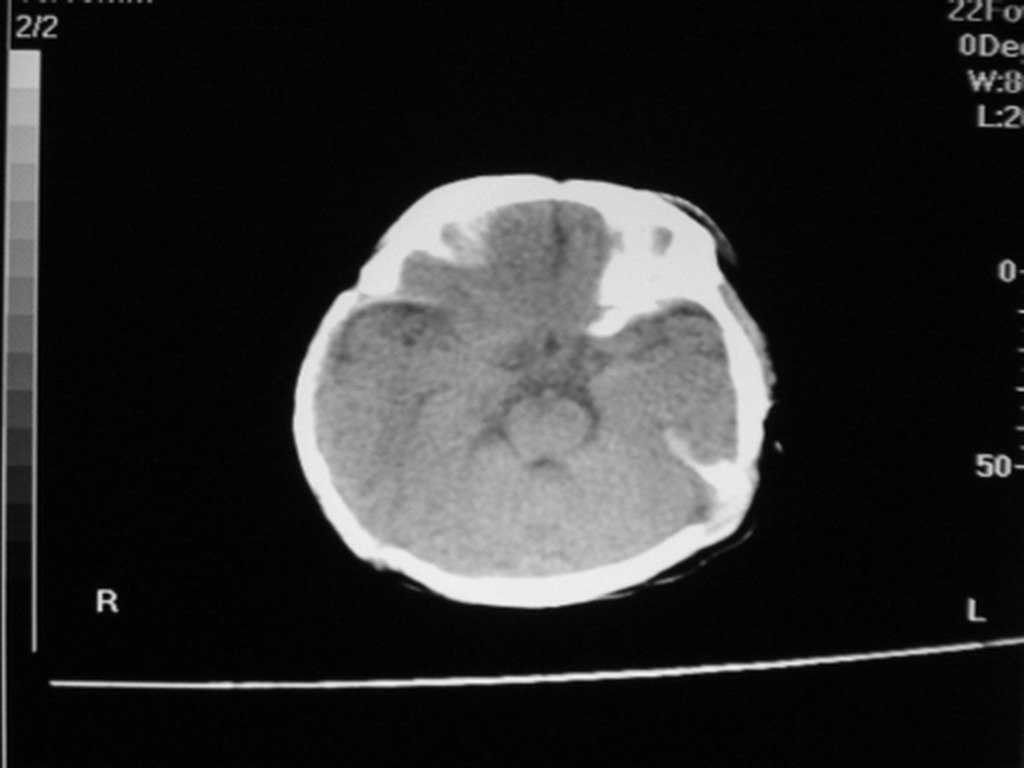

标题: PED1877:女,20余天,突发抽搐,双眼凝视。 [打印本页]

女,20余天,突发抽搐,双眼凝视。